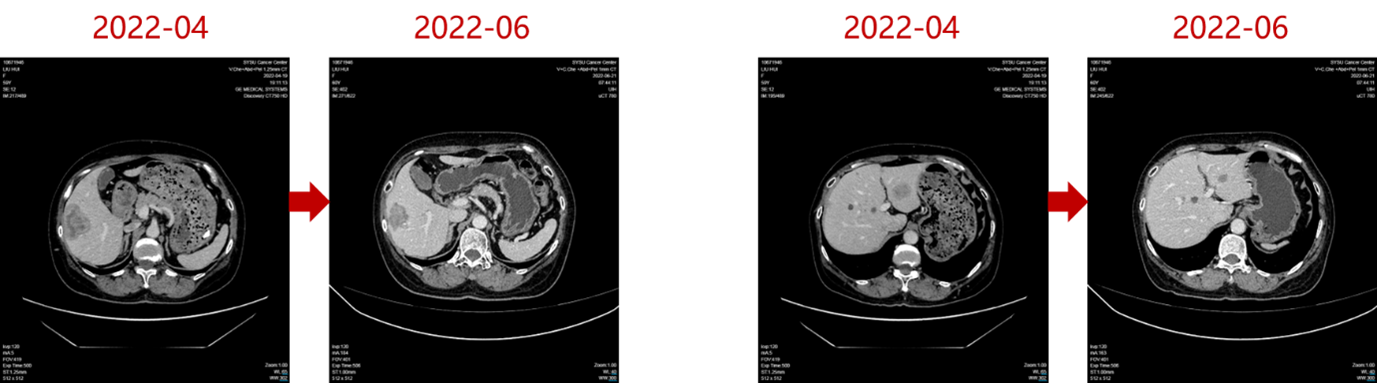

2022年4月27日,患者入组WO41554临床试验,接受“伊那利塞(GDC0077)/安慰剂+哌柏西利+氟维司群”的三靶点联合治疗。仅2个周期后(2022年6月),影像学即显示肝转移灶明显缩小;后续多次评估均维持部分缓解(PR)。

截至2025年9月,患者无进展生存期(PFS)已超过40个月,远超INAVO120研究报道的中位PFS 17.2个月。